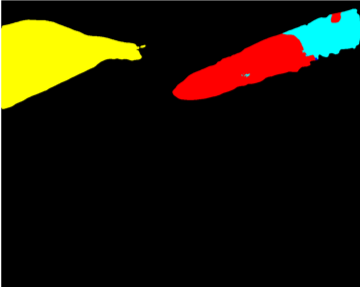

Our challenge was made up of 3 sub-problems. The first was binary instrument segmentation, where each frame was separated into da Vinci Xi instruments and a background class, which contained an ultrasound probe, surgical clips and porcine tissues. The second task was instrument part segmentation, where we scored the participants on whether they could correctly segment each articulating part of the instrument (see Fig. 3). Our final task was to segment and classify the instruments (see Fig. 4).

We provided the first 225 frames of 8 sequences as training data and kept the last 75 frames of those 8 sequences as test data. 2 of the full 300 frame sequences were kept as test sequences. Test labels were kept hidden from the participants. Our datasets contain 7 different robotic surgical instruments. The Large Needle Driver, Prograsp Forceps, Monopolar Curved Scissors, Cadiere Forceps, Bipolar Forceps, Vessel Sealer and additionally a drop-in ultrasound probe, which is typically held in the jaws of the Prograsp Forceps instrument. Samples from the training datasets are depicted in Fig. 2 and examples of the different instrument types are shown in Figure 3 and 4.

IV-D Type Segmentation

The final challenge was to identify each instrument type from the list of Large Needle Driver, Prograsp Forceps, Monopolar Curved Scissors, Vessel Sealer, Fenestrated Bipolar Forceps and Grasping Retractor (see Fig. 4). Only 6 teams participated in this challenge, due particularly to the significant increase in difficulty in recognizing many of the da Vinci instruments from one another.